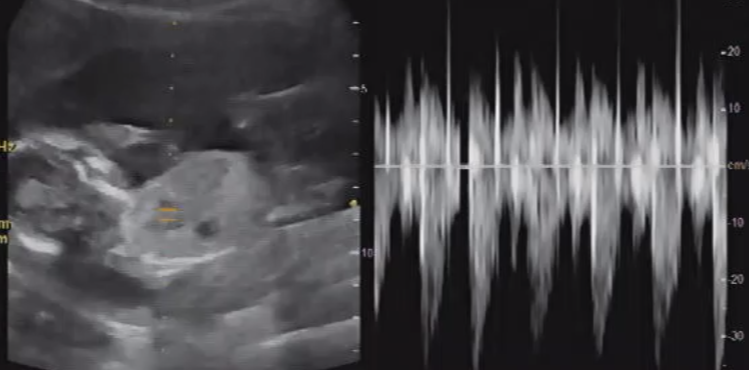

* '19.12/13(16주차) 초음파 사진

선생님께서 초음파 검사 하시면서 엄청 상세하게 설명을 해주십니다.

손가락, 발가락 개수도 5개씩 있고, 아기가 건강하게 잘 크고 있다고 하십니다.

그리고.. 우리 아기.. 치마 선물 해주려구요.^^

저.. 딸바보 되나봐요.!!!